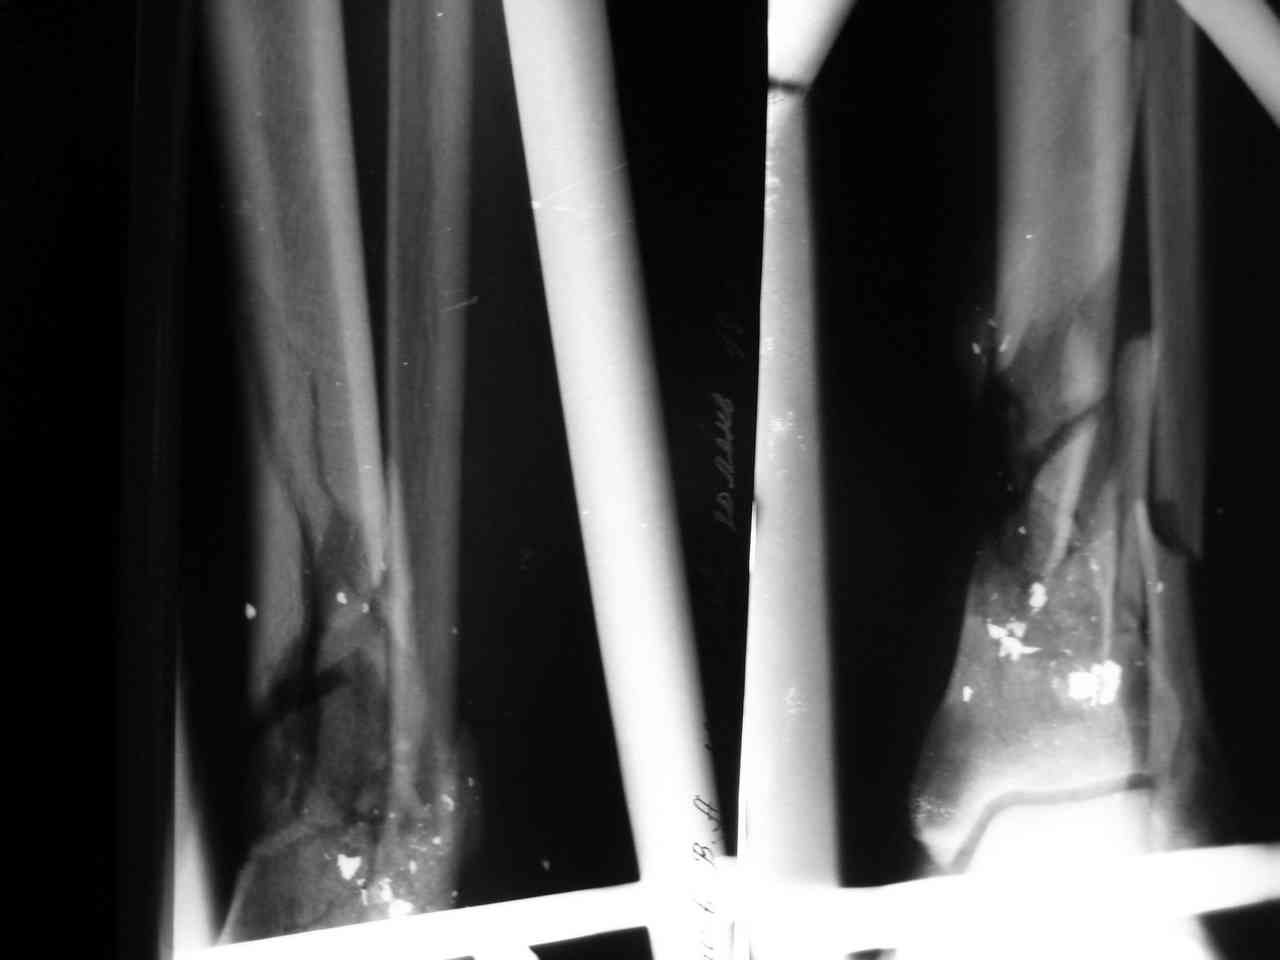

Уважаемые коллеги - нужна консультация. Больной 1974г.р. DS - Открытый огнестрельный перелом н\3 костей левой голени (3В по Каплану) с повреждением задней б\берцовой артерии,вен.Травматический шок 2ст.

Еще находится в отделении пациент со схожим огнестрельным переломом обеих костей нижней трети голени (классификация Каплана, Марковой относится к неогнестрельным переломам). При поступлении

(26/12/2007)выполнена ПХО перелома: выброшены свободно лежащие осколки, иссечены явно нежизнеспособные ткани, наложен двуплоскостной двустержневой аппарат наружной фиксации. Раны не ушивались. Было повреждение передней большеберцовой артерии, вен. Но стопа оставалась

"живой":теплая на ощупь, сохранялась ее чувствительность, активная подвижноть пальцев. На следующие сукти выполнен second look: удалены абсолютно все осколки (если при поступлении они были интимно фиксированы к мягким тканям, что создало обманчивое впечатление их жизнеспособности, то сутки спустя они все оказались свободнолежащими), выполнено резецирование краев отломков для формирования торцевого упора, налажено сквозное дренирование раны.

наложен аппарат ЧКДО по Илизарову под билокальный остеосинтез. Как будут снимки - выложу все.